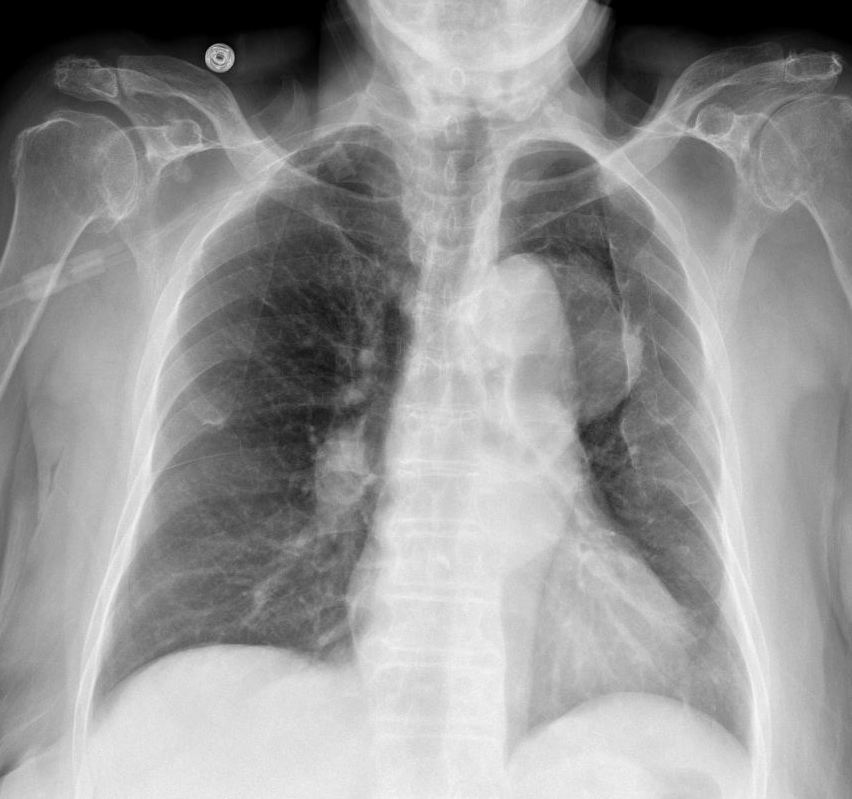

Phình ĐM chủ ngực

» Thông tin: Nam giới – 65 tuổi.

» Lâm sàng: Đau ngực.